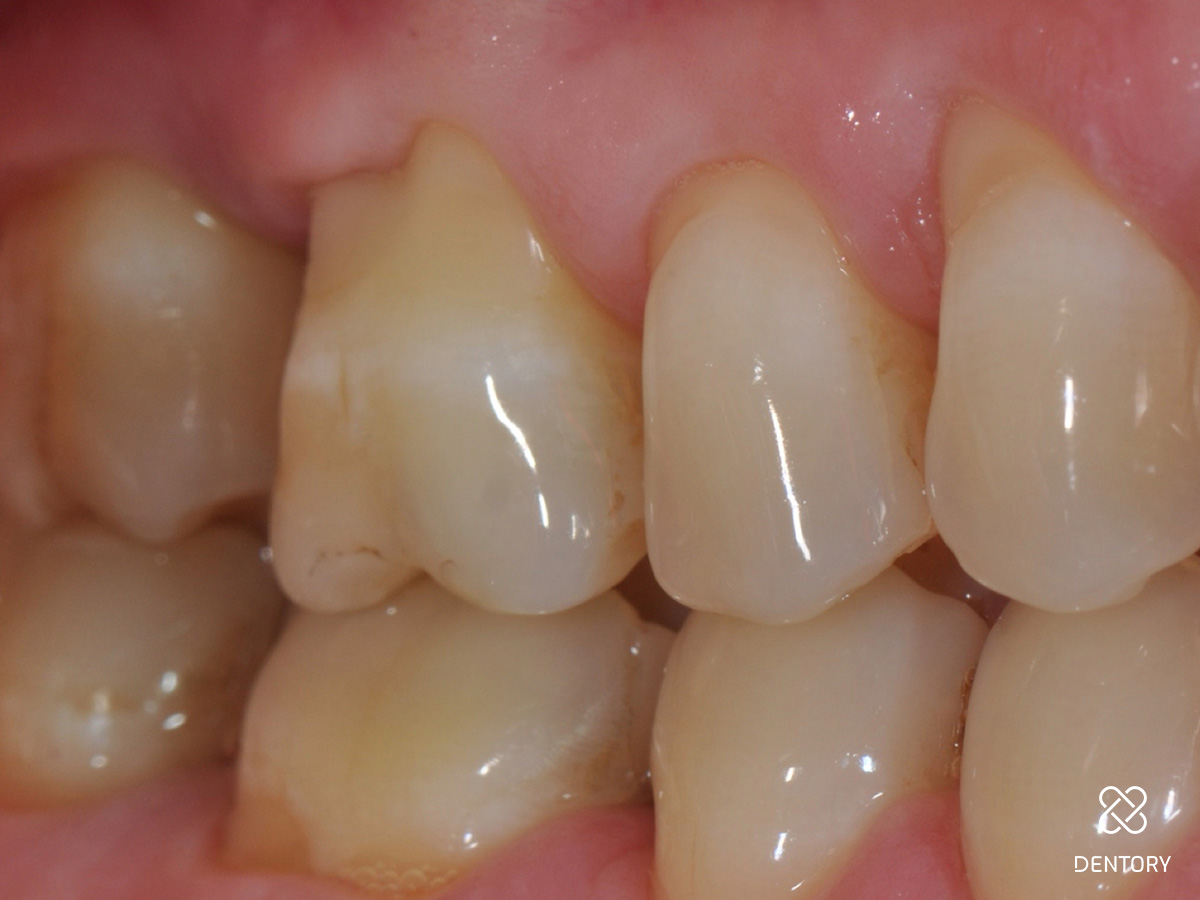

Abbildung 5

Mit einem feinen Raspatorium oder einem Papillenelevator wird ein Mukoperiostlappen zur Darstellung der knöchernen Strukturen präpariert. Die Präparation beginnt idealerweise von einer gut tastbaren Knochenkante zum Defekt hin.